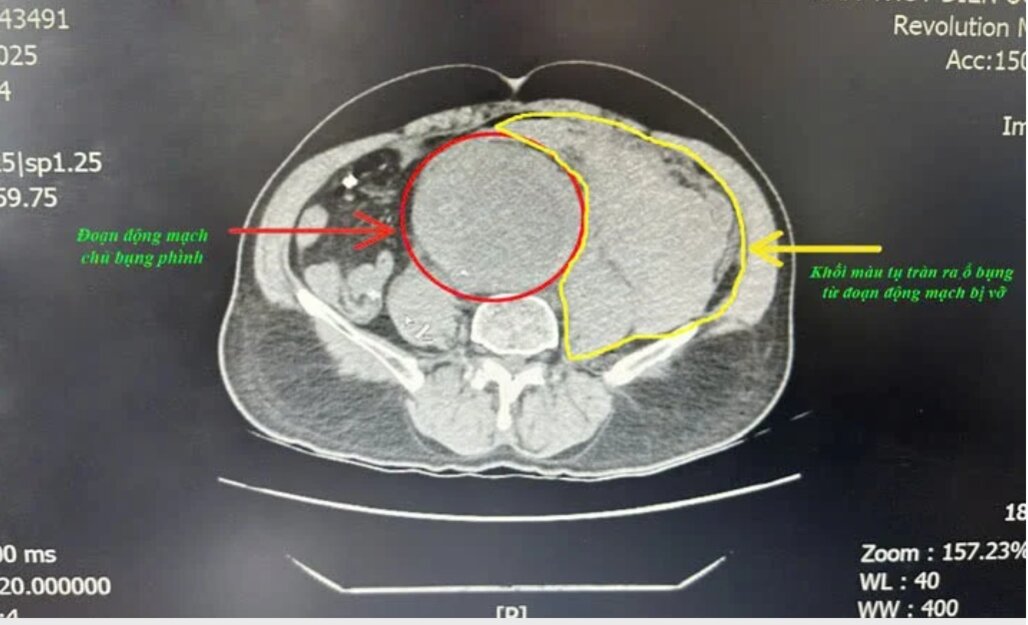

Hình ảnh chụp CT.Scanner của người bệnh. Ảnh BVCC

Tại bệnh viện, ông Khiêm có biểu hiện đau bụng dữ dội, da xanh nhợt, mạch không bắt được, huyết áp không đo được. Kết quả chụp CT.Scanner phát hiện phình động mạch chủ ngực đoạn dưới thận lan đến động mạch chậu 2 bên, khối phình đã vỡ gây tụ máu sau phúc mạc số lượng lớn.